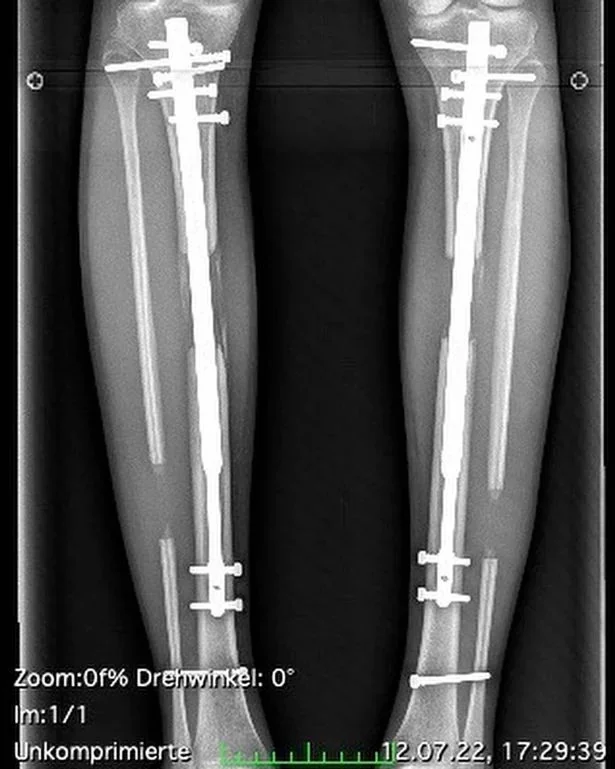

وأوضحت عارضة الأزياء أنها خضعت لعمليتين لإدخال قضبان تلسكوبية في ساقيها يصل ارتفاعها إلى 6 أقدام “1.8288 متر”.